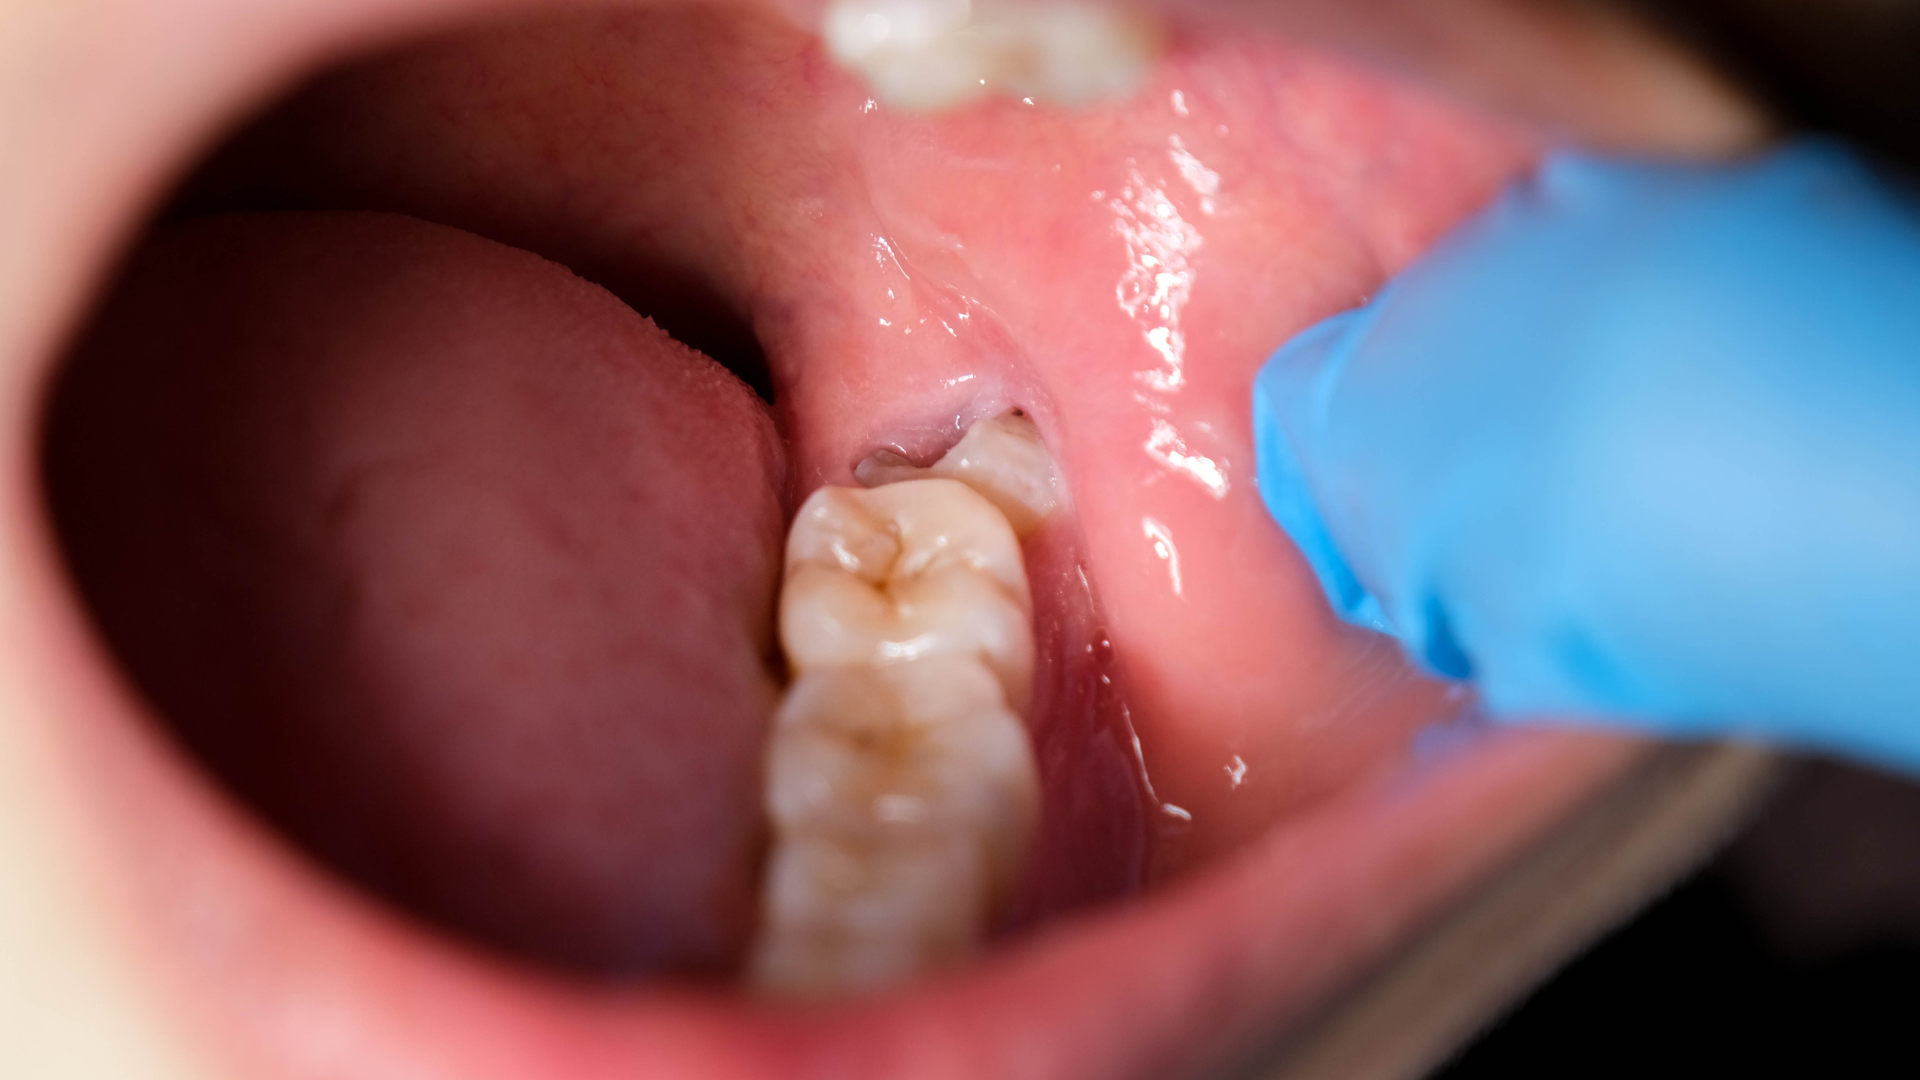

Khi đến khám với nghi ngờ có hay không tình trạng mọc 5 răng khôn, người bệnh sẽ được bác sĩ thăm khám lâm sàng trực tiếp để đánh giá tình trạng nướu và cung hàm. Bước tiếp theo là chụp X-quang toàn hàm hoặc phim cắt lớp nếu cần để xác định chính xác số lượng, vị trí và hướng mọc của tất cả các răng trong xương hàm. Dựa trên kết quả, bác sĩ sẽ tư vấn kế hoạch theo dõi hoặc can thiệp phù hợp với từng trường hợp cụ thể.